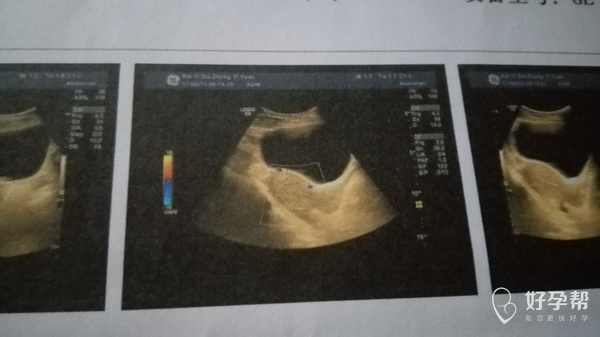

医生麻烦帮我看看这是流干净了吗?

您好,看您的产生报告没有异常的